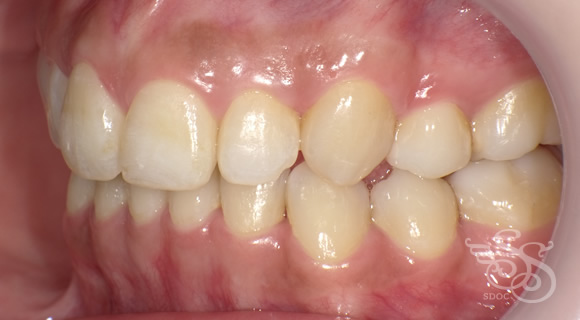

右側:術前

右側:術後

左側:術前

左側:術後